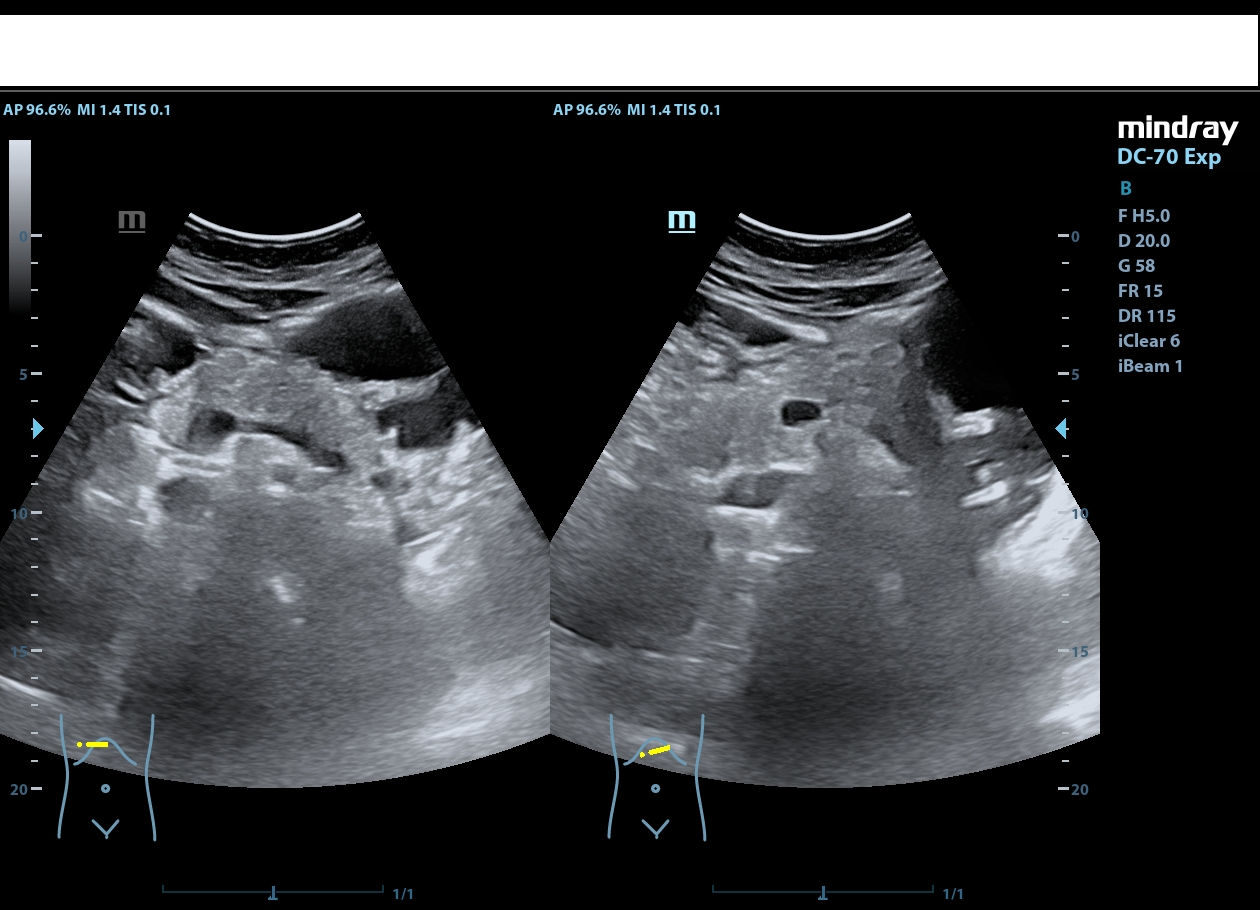

Descripción de los hallazgos ecográficos y las imágenes más relevantes para la resolución del caso

Riñón derecho de ecoestructura conservada, con dilatación pielocalicial grado I. Riñón izquierdo con adelgazamiento cortical y ureterohidronefrosis grado IV, sin poder localizarse el origen de la obstrucción, ausencia de jet ureteral izquierdo. Hallazgos sugestivos de síndrome de la unión pieloureteral.